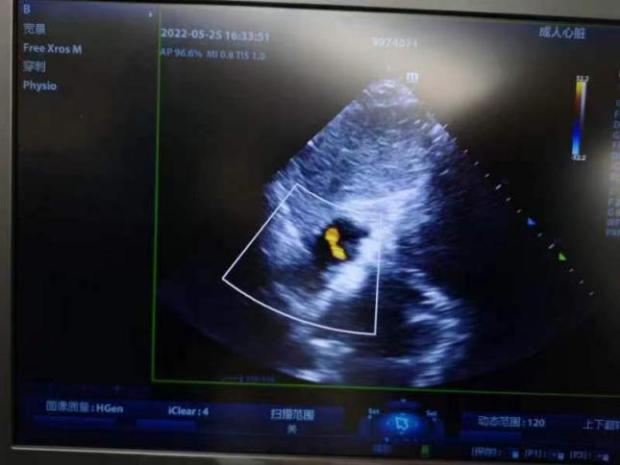

手术在局麻下进行,右股静脉穿刺后,行右心导管检查评估肺高压、肺毛细血管楔压和右房压,计算肺阻力和心排量,然后再经胸超声引导下穿刺房间隔,测量左房压力、左向右压差符合左心衰血流动力学障碍特点,不合并毛细血管前性肺高压。确定合适规格的心房分流器,选择8mm高压球囊扩张后,送入6mm分流器释放于房间隔两侧。推拉试验分流器固定稳定、位置良好,透视下孔径符合预期目标,测量左房压、肺动脉压均较植入前下降,右房压无升高,左向右分流为少量,床旁超声可见分流器夹持于房间隔两侧,分流流速1.4m/s。评估达到预期效果,释放分流器。术后12h患者下床活动,无任何胸闷、头晕不适,活动量较术前改善,六分钟步行距离446米。目前患者已顺利出院,期待后续随访情况。

图1术中操作